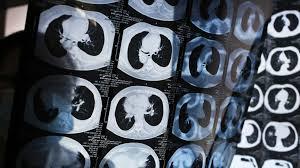

The AI solution, called Doctor You, can be used for medical image diagnosis of CT scans to identify inflammatory cells in human organs, which can be an early indicator of cancer.

“It will soon serve as an assistant to physicians at a number of hospitals in the country,” said Ke Yan, a vice president with Ali Health, adding that the technology could lower error rates, improve efficiency and take over half of the workload from doctors in China within the coming decade.